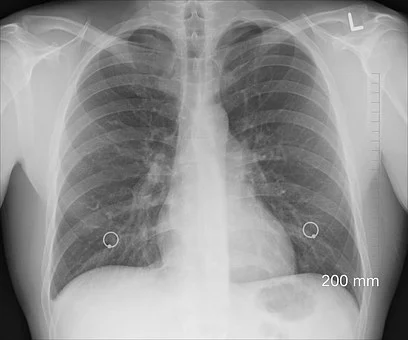

3. 호흡 장애

환자의 절반 이상은 호흡 장애를 겪는다고 합니다. 폐에 문제가 생겼기 때문에 기관지도 좁아지게 되고 호흡을 제대로 할 수 없게 됩니다. 운동을 하지 않았는데도 갑자기 숨이 차거나 가슴의 답답함을 느낀다면 폐암초기 증상을 의심해보셔야 합니다.